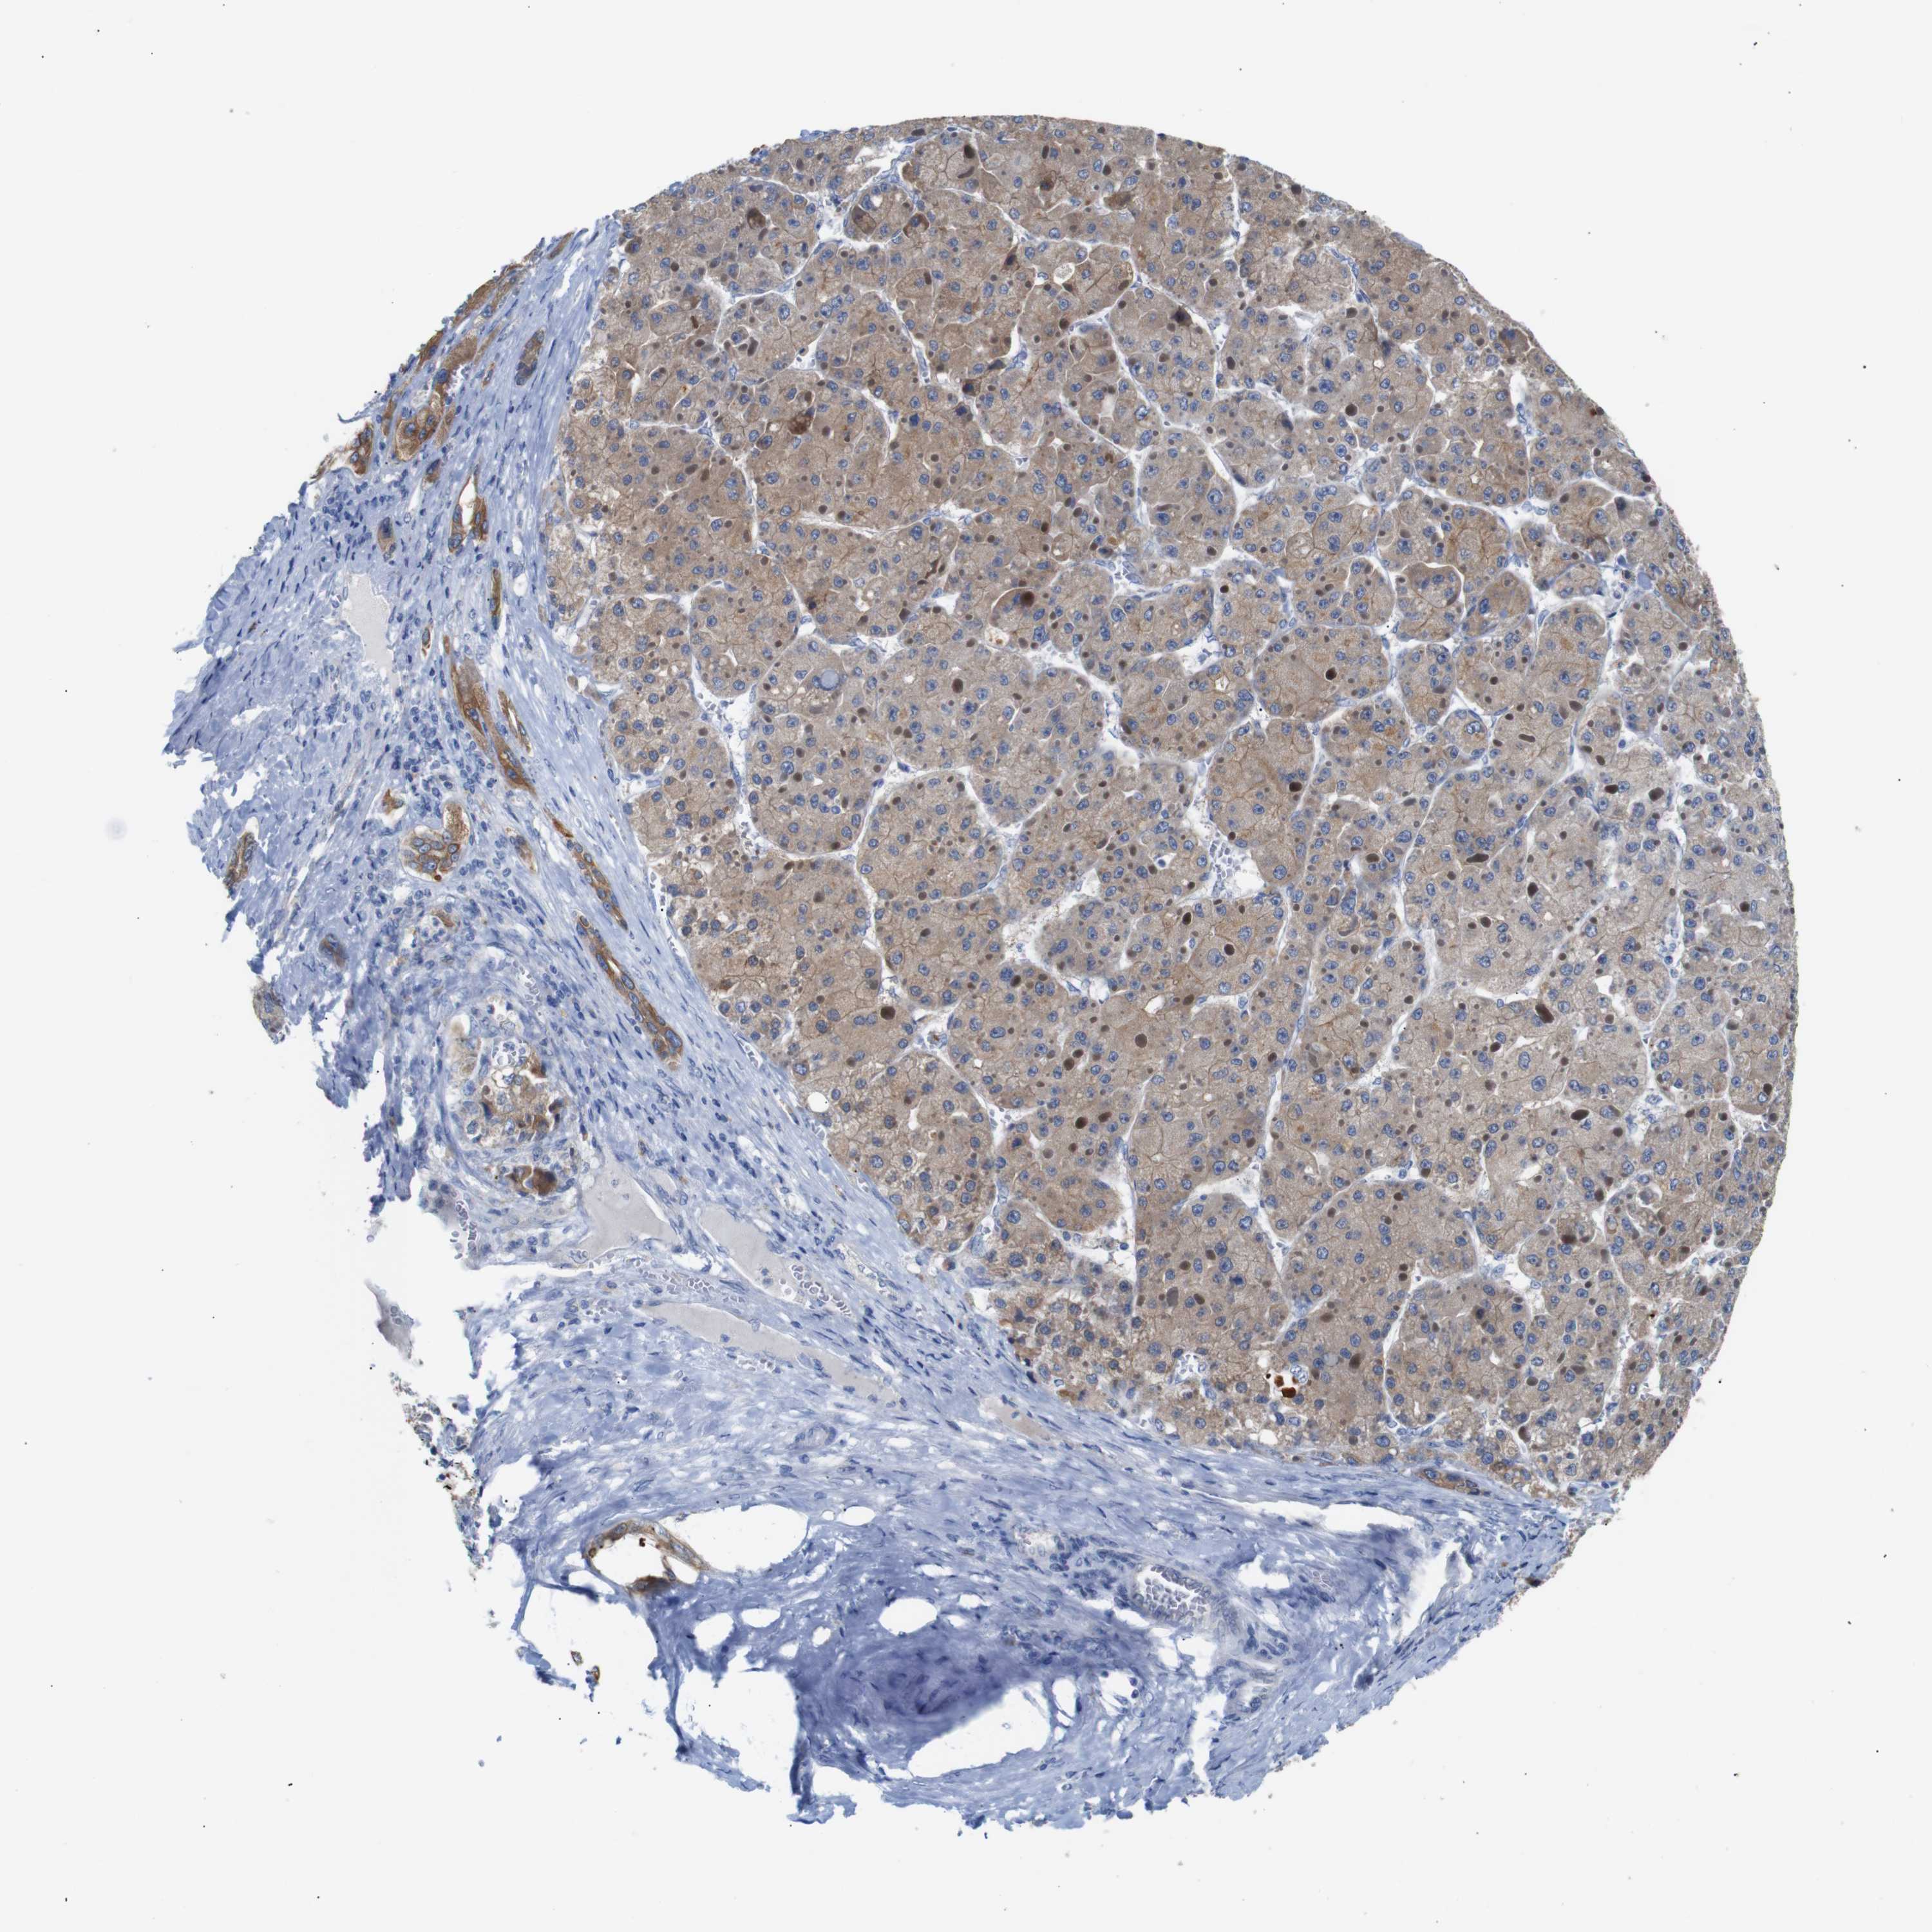

LIVER CANCER - Protein expressioni

A mouse-over function shows sample information and annotation data. Click on an image to view it in a full screen mode. Samples can be filtered based on level of antibody staining by selecting one or several of the following categories: high, medium, low and not detected. The assay and annotation is described here.

Note that samples used for immunohistochemistry by the Human Protein Atlas do not correspond to samples in the TCGA dataset.

Antibody stainingi

Antibody staining in the annotated cell types in the current human tissue is reported as not detected, low, medium, or high, based on conventional immunohistochemistry profiling in selected tissues. This score is based on the combination of the staining intensity and fraction of stained cells.

Each image is clickable and will lead to virtual microscopy that enables deeper exploration of all samples and also displays staining intensity scores, fraction scores and subcellular localization as well as patient and tissue information for each sample.

Antibody HPA013859

Antibody CAB004962

Antibody CAB004963

Staining

High

Medium

Low

Not detected

Intensity

Strong

Moderate

Weak

Negative

Quantity

>75%

75%-25%

<25%

None

Location

Nuclear

Cytoplasmic/membranous

Cytoplasmic/membranous,nuclear

Cholangiocarcinoma

Carcinoma, Hepatocellular, NOS